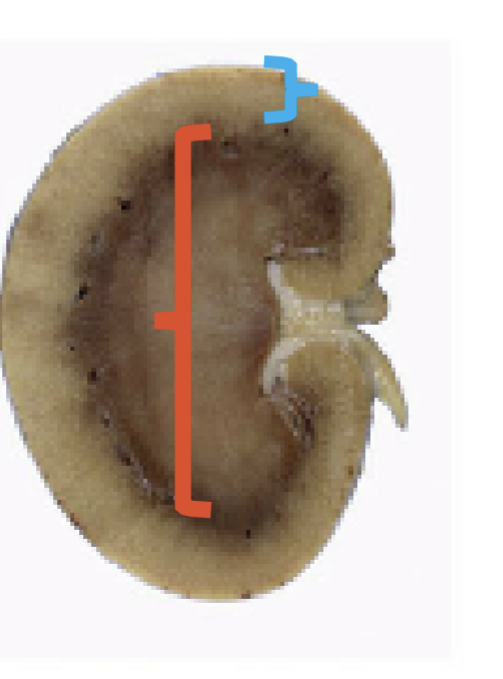

Red arrow?

Renal papilla

Yellow arrow?

Renal Calyx

#1?

Renal Pelvis

#2?

Renal pyramid

#3?

Renal capsule

Renal Hilus

Blue?

Renal cortex

Red?

Renal medulla